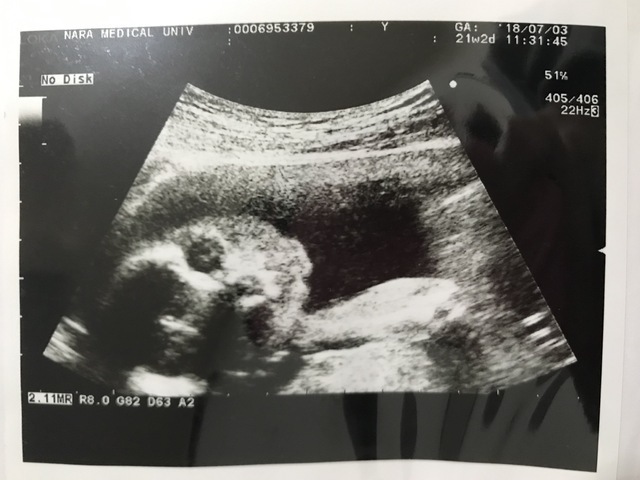

21週2日(21w2d・女の子)|なりんこ さん(30歳)

エコー写真撮影時のエピソード:

既にたくさん動いていたので4Dでもその様子が見れるとワクワクしてたのですが、おもいっきりお休み中...zzZ でも可愛く顔の前で腕組んで寝てる姿が可愛くって、また愛しさが込み上げました。またこの頃、市のパパママ教室に参加し、新生児の抱き方、オムツの変え方、パパの妊婦さん体験などを通して夫婦で勉強しました。見せていただいたビデオの影響からか、パパは毎朝晩欠かさずベビちゃんに話しかけてます。生まれる前から夫婦揃ってメロメロです(●´ω`●)